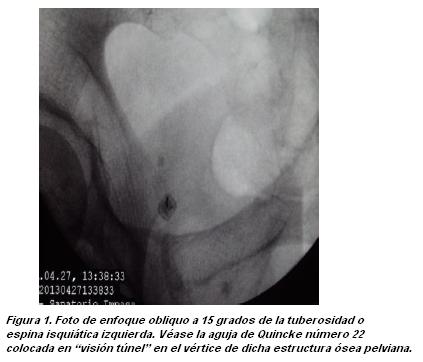

A la semana el paciente presentó alivio de más de un 50% de su dolor inicial, con mejoría funcional importante, respuesta de aproximadamente 4 a 6 semanas de duración. Dos semanas después se repite procedimiento con respuesta evolutiva similar. Se plantea la realización de una radiofrecuencia pulsada de ambos nervios pudendos. En condiciones previas similares a las descritas para el bloqueo con anestésicos locales, se punciona con cánula de radiofrecuencia número 22 de 10 de cm con 1 cm de punta activa, dirigiendo con visión túnel hacia el vértice de la espina isquiática derecha (figura 2) hasta hacer contacto óseo. Luego se realiza prueba sensitiva con siendo positiva a 0.5 milivoltios. El paciente relato dolor a nivel perineal, en la misma topografía que el dolor que motivo su consulta. Se realizó 2 cc de lidocaína al 0.5%. Se comprobó nuevamente posición de la aguja en espina isquiática en con arco en C en posición oblicua y perfil (figuras 2 y 3). A continuación se realizaron dos sesiones de radiofrecuencia pulsada de 120 segundos cada una a 45 a 50 voltios, 42 grados de temperatura. Luego se inyectaron 5 cc de una solución de lidocaína al 0.5 % mas 25 mg de triamcinolona. Se procedió del mismo modo del lado contralateral. También en este caso se obtuvo respuesta sensitiva a la estimulación a 0.5 voltios, despertando dolor de las mismas características a nivel perineal. El procedimiento se desarrollo sin incidentes. El paciente presentó los días siguientes un incremento moderado de su dolor, retornando luego éste a sus condiciones basales. Este incremento del dolor luego del procedimiento se tomó como limitante para repetir un nuevo intento de radiofrecuencia.